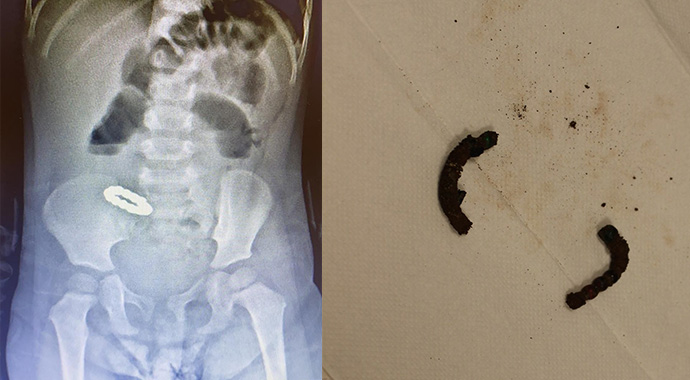

Minik Beren’in getirildiğinde genel durumunun kötü olduğunu belirten Doç. Dr. Özdemir, “Bana bebeğin mıknatıs yutmuş olduğu söylendi. Çektiğimiz karın filminde bilezik şeklini almış küçük yuvarlak mıknatıslar görülüyordu. Hastanın bağırsak tıkanıklığı olduğunu saptadık. Hastanın beslenememesinin nedeni de bu bağırsak tıkanıklığıydı. Ameliyatta ince bağırsakların birkaç yerde birbirine yapışmış olduğunu, ince bağırsakların diğer kısımlarının da bu yapışıklıkların arasına sıkışmış olduğunu gördük. Yapışmış olan bağırsakları birbirinden ayırdığımızda, bu bağırsaklarda 6 adet delik olduğu, bu deliklerden uç uca birbirine tutunmuş küçük mıknatıslar çıktığı görüldü. 12 adet mıknatıs çıkardık. Ama bağırsakta başka mıknatıs kalıp kalmadığından emin olmak için tüm bağırsağı titizlikle tekrar tekrar inceledik. Başka bir mıknatısa rastlamadık. bağırsağın delikler açılmış olan iki bölgesi, 10 cm ve 12 cm’lik parçalar halinde çıkarıldı. İnce bağırsaklar iki bölgeden tekrar birbirine dikilerek bağlandı. Hastamızın bağırsakları 6. günde tekrar çalışmaya başladı. Yemek yiyebilir hale gelen hastamızı, şifa ile taburcu ettik” dedi.